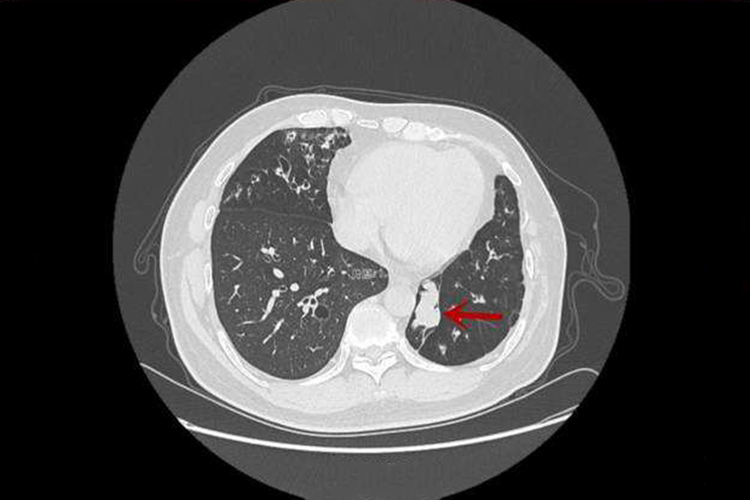

痰栓由黏稠的痰液、脱落的上皮细胞、白细胞、吞噬细胞等成分共同缠绕包裹而形成,外观为黄白色柱状物,可有血丝附着,影像学检查可见肺纹增粗或小斑片状阴影,临床上表现为口唇或肢体发绀、气急症状。